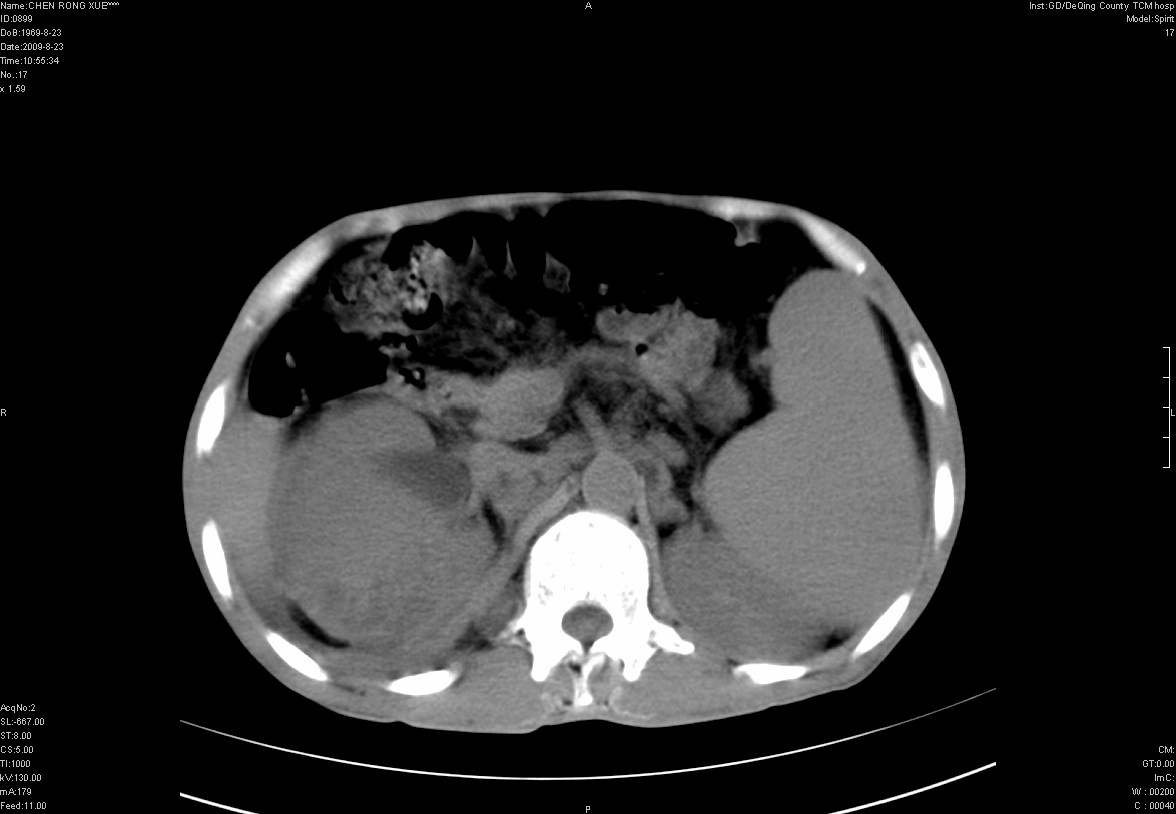

以下是引用zxl51642在2009-8-23 12:56:00的发言:[br]1、肝硬化、脾大;2、慢性胆囊炎;3、右肾占位并右侧腰大肌受侵,考虑恶性可能性大,建议增强扫描进一步检查。

以下是引用qiuleiyu在2009-8-23 15:17:00的发言:[br]1、慢性肝病,肝硬化,脾大,门脉高压。胆囊小结石。[br]2、右肾明显肿大,伴片状低密度灶,累及右侧腰大肌,肿瘤及炎症性病变皆有可能大,建议增强。

以下是引用zjzjr在2009-8-23 17:42:00的发言:[br]1、慢性肝病,肝硬化,脾大,门脉高压。胆囊小结石。[br]右肾脓肿波及肾周,建议增强

以下是引用dyqct在2009-8-23 16:53:00的发言:[br][quote]以下是引用qiuleiyu在2009-8-23 15:17:00的发言:[br]1、慢性肝病,肝硬化,脾大,门脉高压。胆囊小结石。[br]2、右肾明显肿大,伴片状低密度灶,累及右侧腰大肌,炎症性病变可能,建议增强。